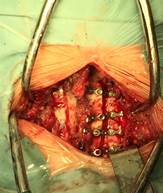

Una vez lograda una apertura satisfactoria se procede a la estabilización con osteosíntesis. Utilizamos mini placas Martin de titanio con tornillos laminoarticulares (5 a 9 mm de longitud) Figura 3.

Figura 1: Procedimiento quirúrgico: disección, osteotomías y estabilización con mini placas, tornillos lamino articulares